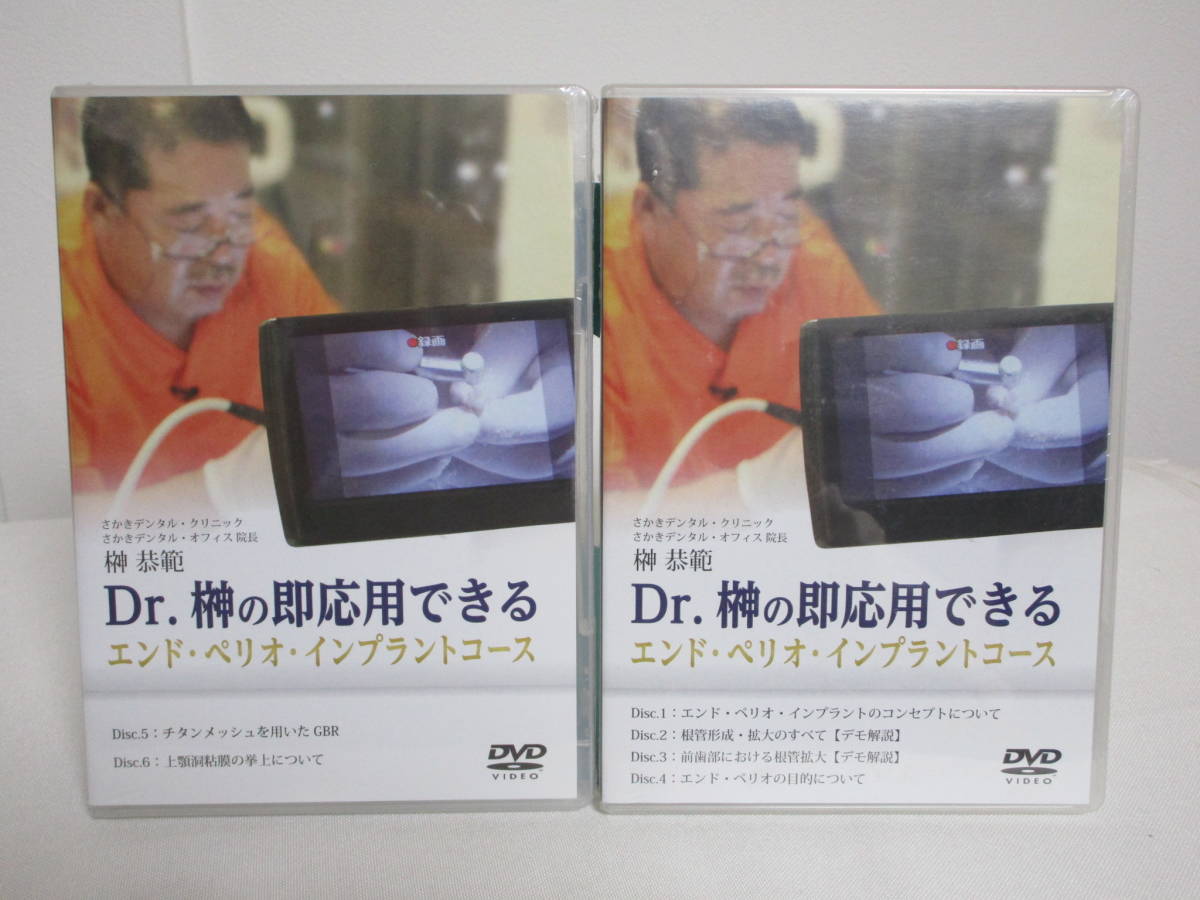

INTENTIONAL EXTRUSION 意図的挺出の現在 一般診療におけるエクストルージョンの現在 改定新版 1997年発行 送料370円 【a-4058】

エクストルージョン(歯根挺出)3 | 稲城市のランドマーク歯科クリニック,歯根だけでも抜歯にならない!エクストルージョン法(矯正的歯の廷出)症例 | 横浜市東戸塚駅より徒歩1分の歯科医院,エクストルージョン—新馬場・北品川の歯医者ならかなもり歯科クリニック|品川区|大田区,エクストルージョン(歯根挺出術)|徳島 米沢歯科クリニック|インプラント・審美・セラミック|歯科医院 歯医者,歯根だけでも抜歯にならない!エクストルージョン法(矯正的歯の廷出)症例 | 横浜市東戸塚駅より徒歩1分の歯科医院